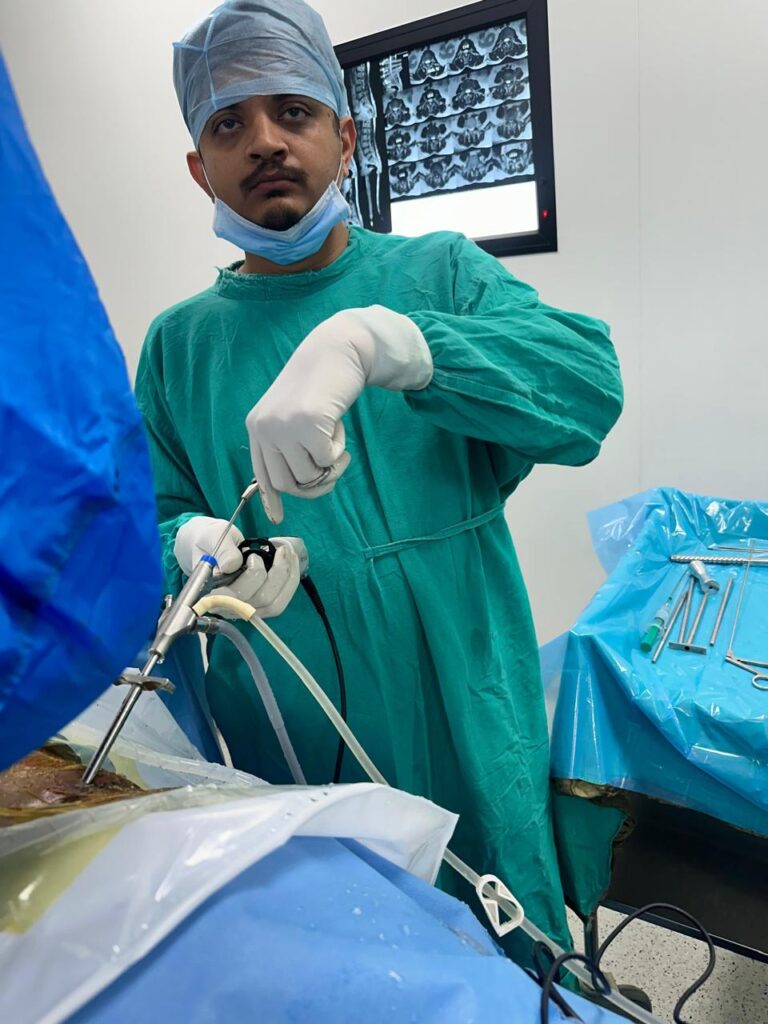

Dr. Ridham Khanderia, MBBS, MS (General Surgery), MCh (Neurosurgery) is a Neuro and Spine Surgeon with over 4 years of clinical experience and more than 2,000 neurosurgical and spine procedures performed. He completed his MBBS from PDU Medical College, MS in General Surgery from MP Shah Medical College, and MCh in Neurosurgery from AIIMS Rishikesh. He also holds a Fellowship in Endoscopic Spine Surgery from Pune.

He specializes in back pain, slip disc, sciatica, and complex spine and brain disorders, with a strong focus on conservative treatment, minimally invasive surgery, and ethical, patient-centered care.